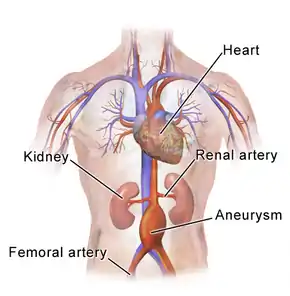

AAAs occur most commonly in men, those over 50 and those with a family history of the disease.[1] Additional risk factors include smoking, high blood pressure, and other heart or blood vessel diseases.[3] Genetic conditions with an increased risk include Marfan syndrome and Ehlers–Danlos syndrome.[4] AAAs are the most common form of aortic aneurysm.[4] About 85% occur below the kidneys, with the rest either at the level of or above the kidneys.[1] In the United States, screening with abdominal ultrasound is recommended for males between 65 and 75 years of age with a history of smoking.[7] In the United Kingdom and Sweden, screening all men over 65 is recommended.[1][8] Once an aneurysm is found, further ultrasounds are typically done on a regular basis.[2]

Hemodynamics affect the development of AAA, which has a predilection for the infrarenal aorta. The histological structure and mechanical characteristics of the infrarenal aorta differ from those of the thoracic aorta. The diameter decreases from the root to the aortic bifurcation, and the wall of the infrarenal aorta also contains a lesser proportion of elastin. The mechanical tension in the abdominal aortic wall is therefore higher than in the thoracic aortic wall. The elasticity and distensibility also decline with age, which can result in gradual dilatation of the segment. Higher intraluminal pressure in patients with arterial hypertension markedly contributes to the progression of the pathological process.[18] Suitable hemodynamic conditions may be linked to specific intraluminal thrombus (ILT) patterns along the aortic lumen, which in turn may affect AAA's development.[29]